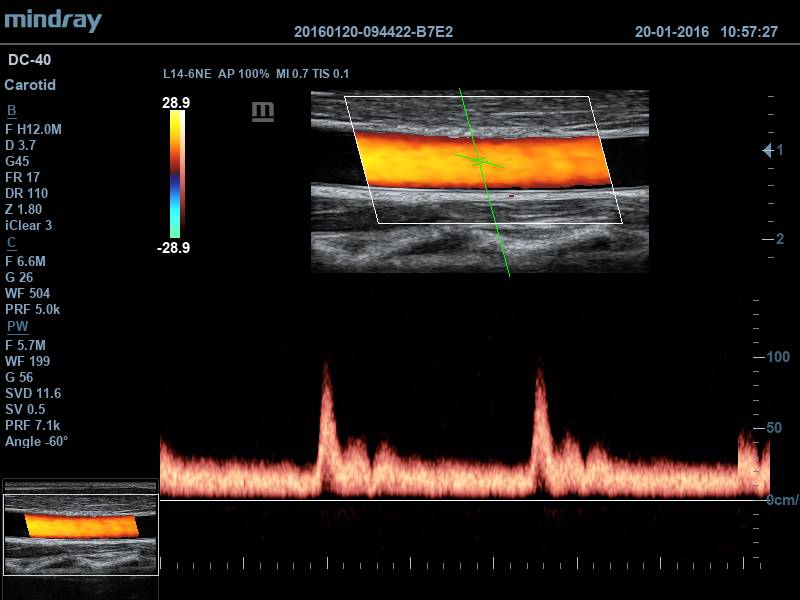

• Режимы визуализации: B/M/Color/Color M/Power/Directional Power Doppler Flow Импульсно-волновой допплер (включая режим высокой частоты повторения импульсов HPRF)

• Smart Track™ - Автоматическая подстройка расположения и угла наклона рамки цветового допплера с автоматическим отслеживанием положения контрольного объема

• Auto IMT Package Программное обеспечение для автоматического измерения толщины комплекса интима-медиа

• Программное обеспечение для автоматического измерения толщины комплекса интима-медиа Программное обеспечение для оценки эластичности ткани методом компрессионной эластографии(поддерживается на датчиках 7L4A, L12-3E and L14-6NE)